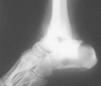

Fig. 12. --Pseudoartrosis y NAV en fractura de cuello de astrágalo. Artrodesis tipo Blair

Fig. 12. --Pseudoarthrosis and avascular necrosis in a fracture of the astragalus neck. Blair-type arthrodesis.